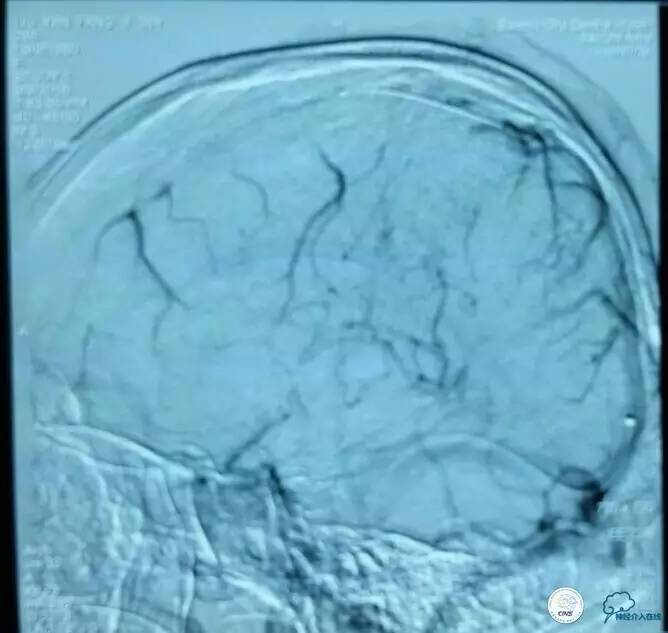

▼导丝,支架位置:

▼支架释放:

▼确定微管位置: